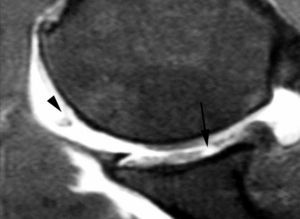

Lesión de Perthes

La lesión de Perthes es similar a la de Bankart, con la excepción de que no existe rotura capsuloperióstica, aunque el periostio puede estar separado del borde anterior del margen glenoideo (fig. 10). Esta lesión puede ser difícil de visualizar, incluso con artrorresonancia, a menos que se obtengan imágenes con la posición de abducción y rotación externa (ABER). En un estudio de 10 casos, verificados quirúrgicamente, Wisher et al17 comprobaron que el 50% de las lesiones de Perthes sólo podían visualizarse en la posición de ABER.

Fig. 10.--Lesión de Perthes. Artrorresonancia T1 con saturación grasa en posición ABER (abducción y rotación externa), donde se observa un arrancamiento parcial del labio glenoideo (flecha) con conservación de la unión capsuloperióstica.